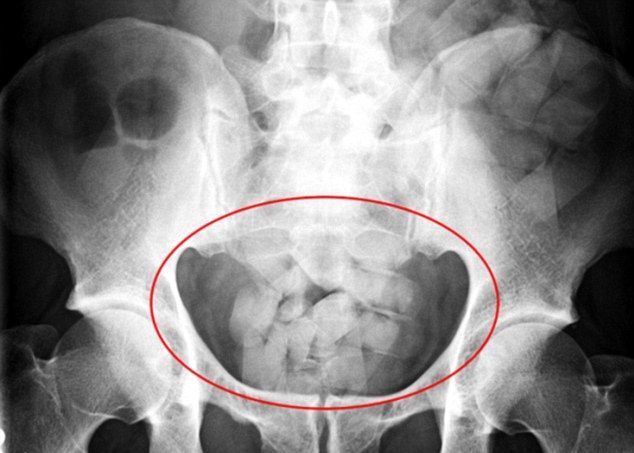

Se trata de tres mujeres de nacionalidad boliviana que fueron detenidas en la Terminal de Ómnibus catamarqueña cuando intentaban viajar a la provincia de San Juan. Las tres bolivianas eran "mulas” que traficaban estupefacientes ilegales dentro de su organismo.